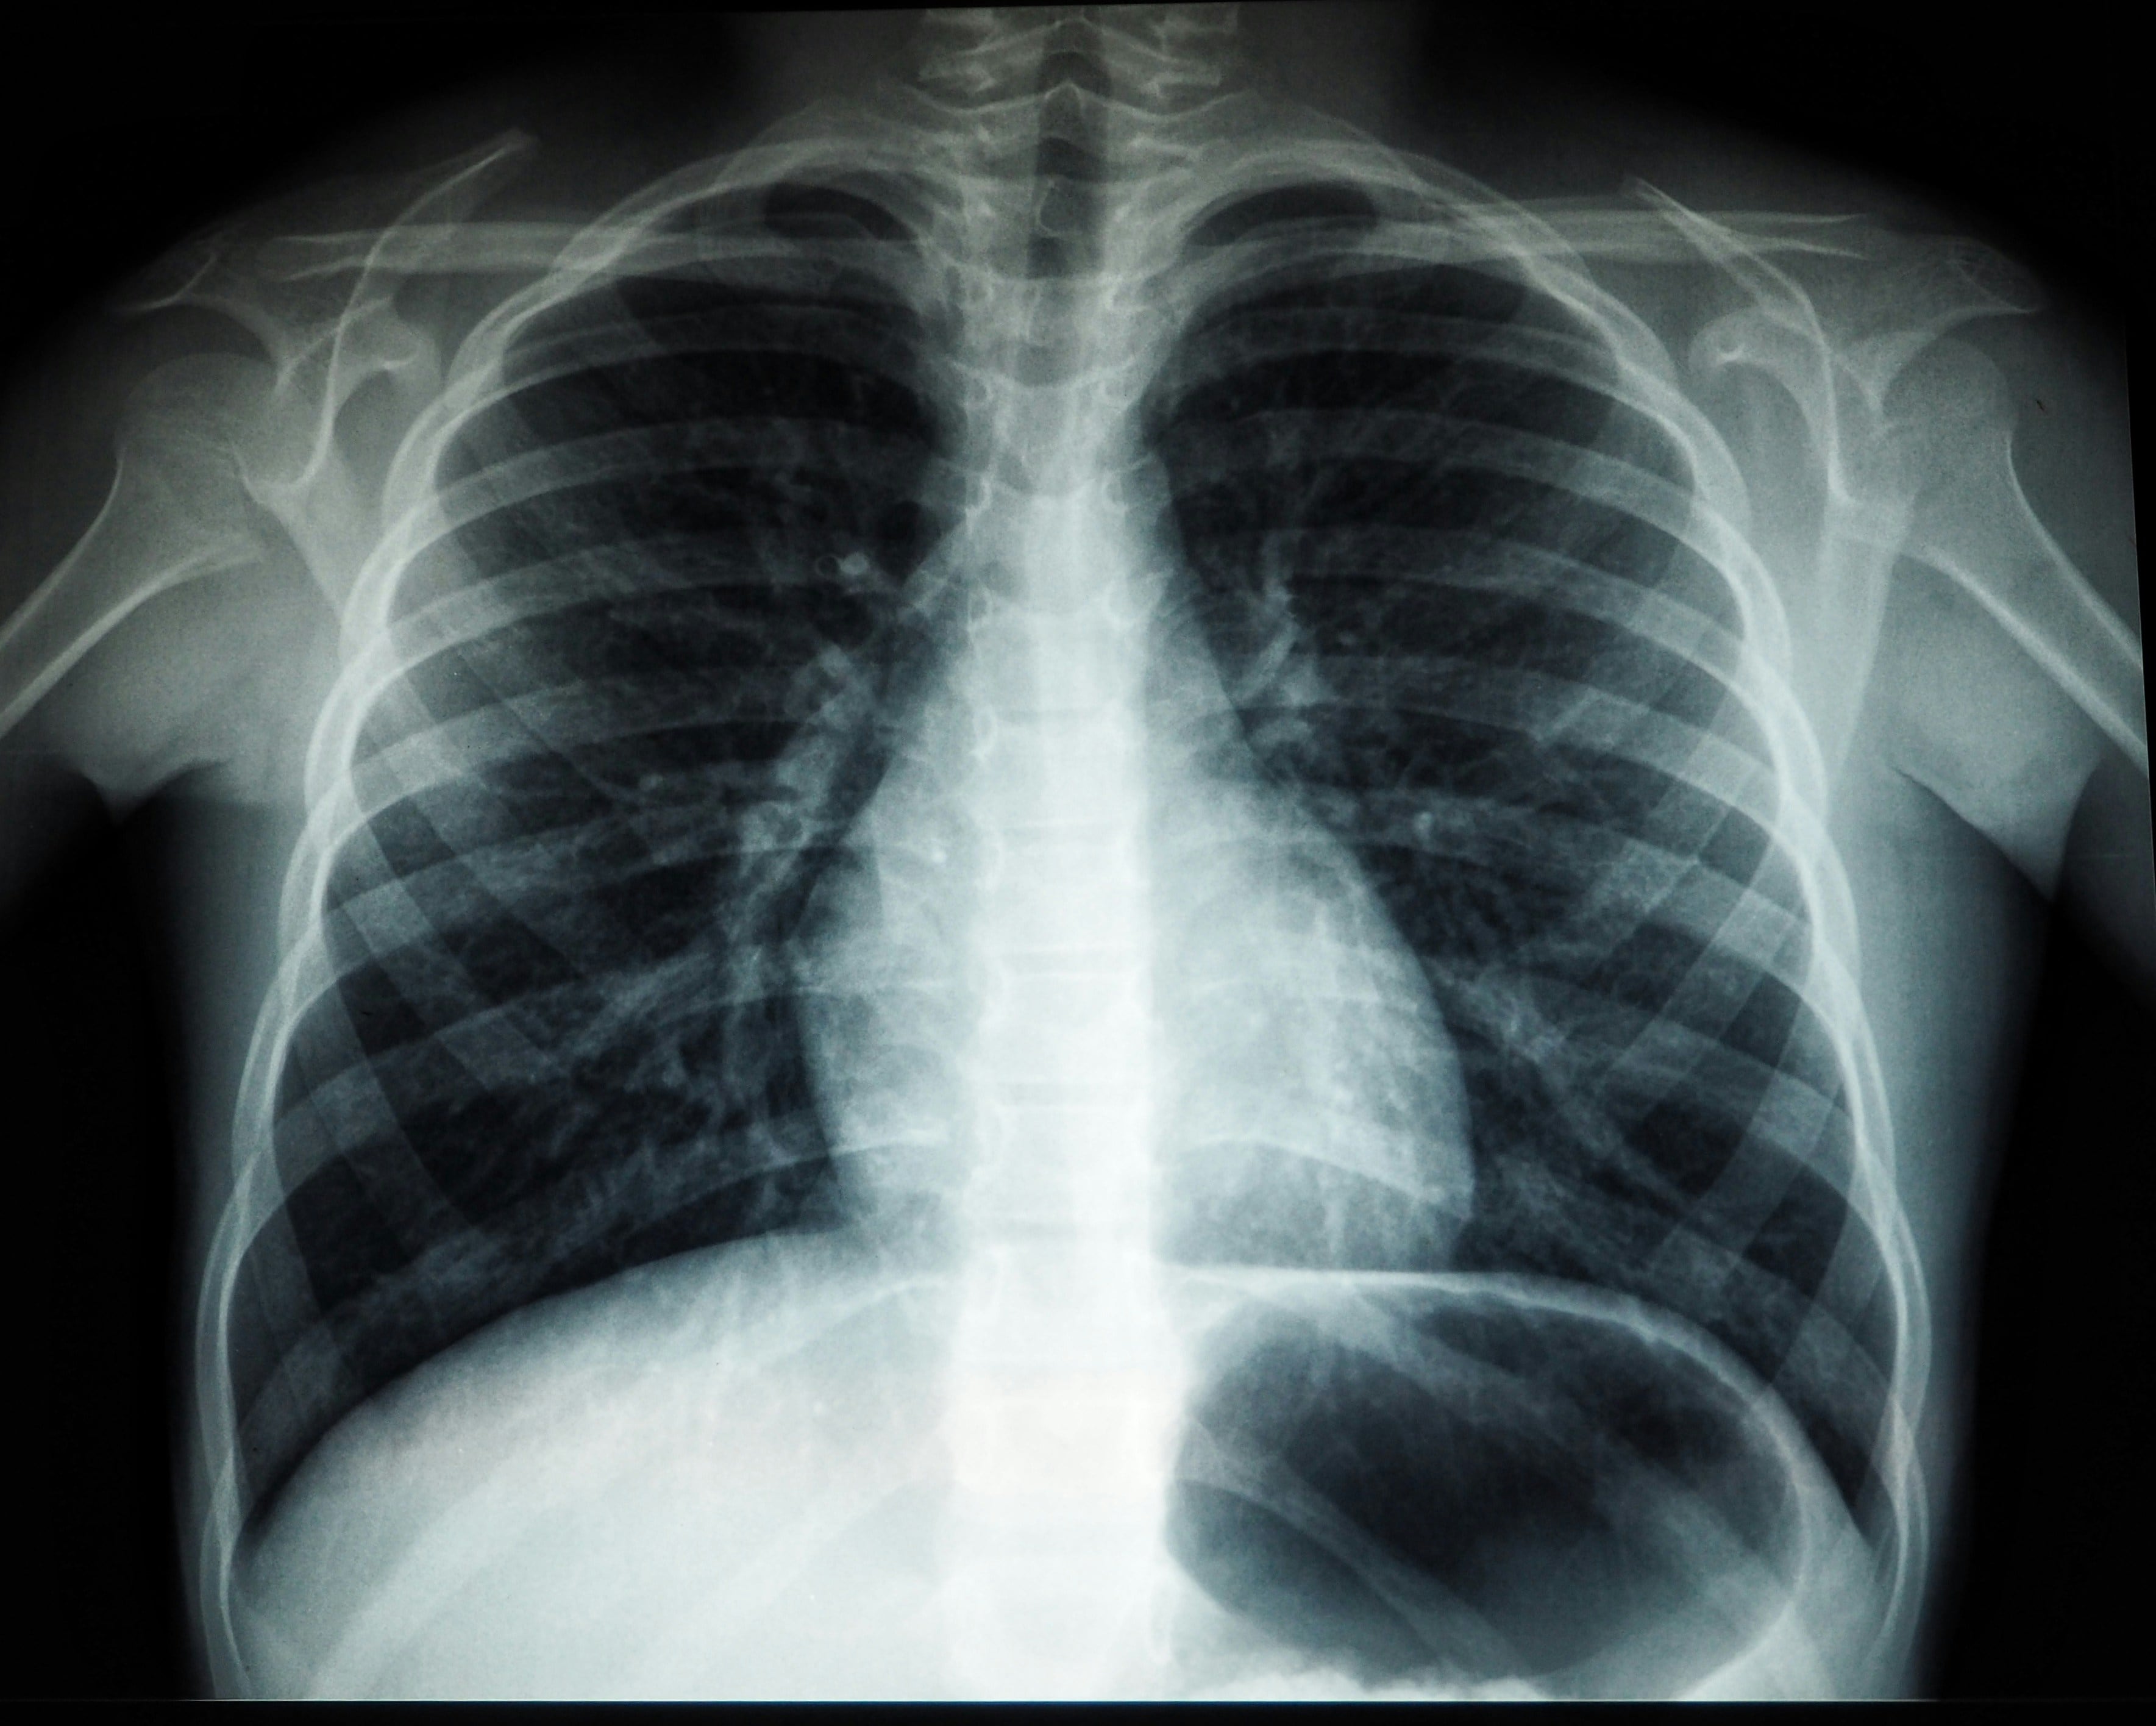

Algunos de los síntomas que pueden generar el polvo del Sahara 2025 a pacientes con problemas respiratorios, son:

- Crisis asmáticas

- Broncoespasmo

- Irritación en ojos, nariz y garganta